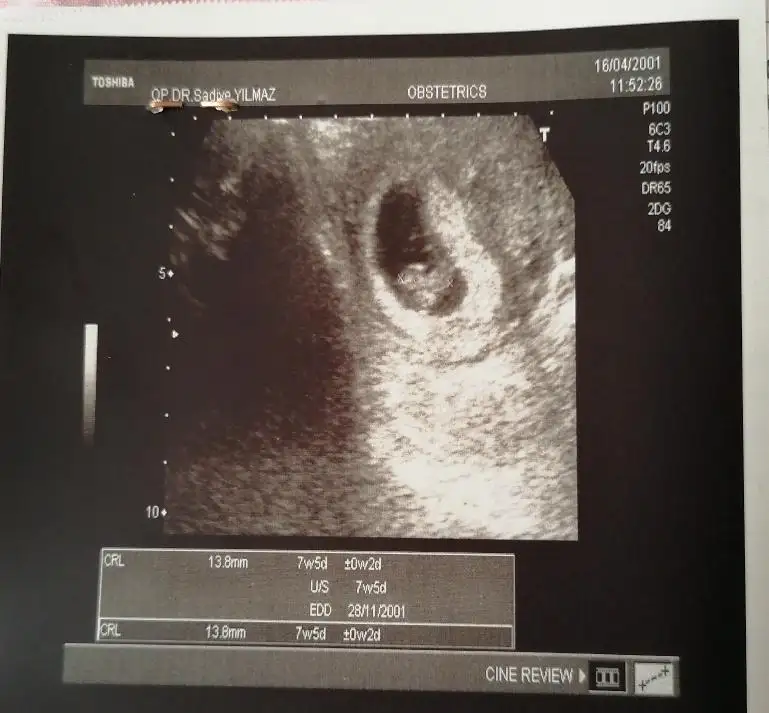

Selam kizlar yil oldu girmeyeli nasilsiniz😍 7 haftalik tahminlerinizi alirim karindan usg sol kesede bekliyorum😘

Ikra meyra Ikra meyra